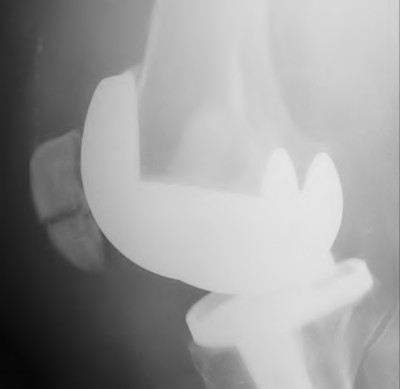

A 65-year-old woman with painful knee arthritis and the deformity seen in Figure A, is scheduled to undergo a total knee arthroplasty. All the following are risk factors for a post-operative peroneal palsy EXCEPT:

Figure A demonstrates and AP radiograph of the knee showing end-stage arthritis with severe lateral compartment narrowing.